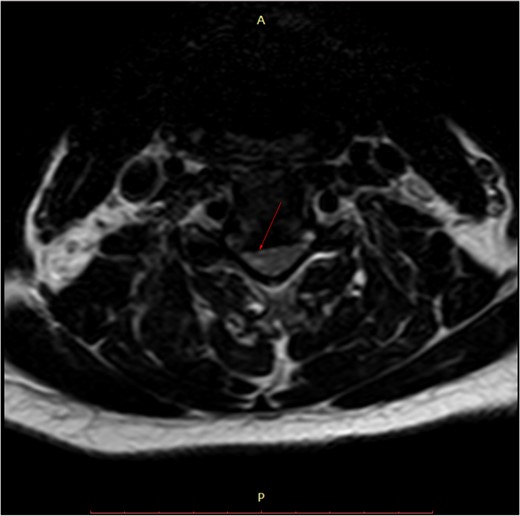

Pre-surgery axial MRI. Arrowhead points towards a focus of hyperintensity at the aforementioned level.

MRI is the study of choice. Some researchers advocate the use of a low focal T1 and/or high T2 signal as a negative prognostic factor regarding post-treatment outcome, while others defy it.